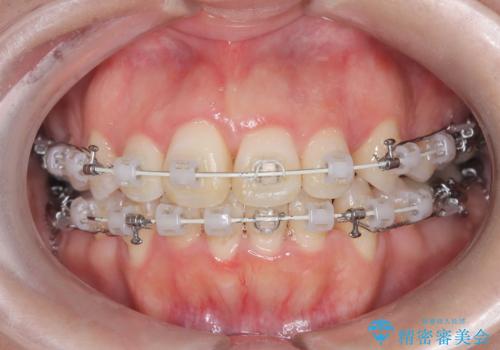

前歯のデコボコと開口を改善し、美しい口元へ

- 前歯のデコボコ(叢生)と、上下の歯が閉じない開口を主訴にご来院されました。精密な検査の結果、歯が並ぶスペースが不足しており、特に奥歯の咬み合わせが安定していないことが開口の原因と判明。患者様と相談し、上下左右の小臼歯を抜歯することでスペースを確保し、審美ワイヤー矯正で全体を整える治療計画を立案しました。これにより、見た目の改善だけでなく、機能的な咬み合わせも獲得することを目指します。

今回の矯正治療では、歯が並ぶスペースを確保するため、上下左右の小臼歯を抜歯しました。装置には目立ちにくい審美ワイヤーを使用し、見た目に配慮しながら治療を進めました。抜歯によってできたスペースを利用して歯を並べ、前歯のデコボコを解消。同時に、歯列全体を動かすことで、上下の歯がきちんと閉じる開口も改善しました。治療期間は約2年間。治療の結果、コンプレックスだった前歯のデコボコと開口が解消され、整った美しい歯並びと、しっかり咬める機能的な咬み合わせを獲得していただけました。